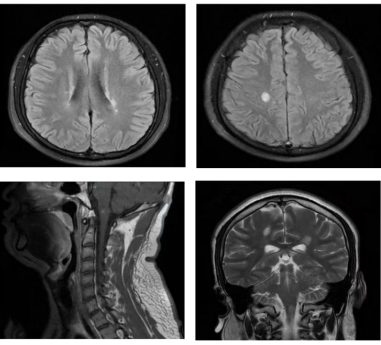

病例一  小崔是一个身强力壮的大四学生,即将离开校园步入社会,一天早上起床感觉头晕,伴有恶心和呕吐,自觉四肢麻木,看东西出现双影,第二天出现走路不稳,在家人的陪同下去了当地县医院,诊断“前庭神经炎”,输液治疗,症状没有明显好转。小崔的母亲非常着急,带着小崔来到沧州市中心医院神经免疫、中枢神经系统感染二科就诊,刘洁琼主任团队通过详细地询问病史、查体,对患者进行了腰椎穿刺显示寡克隆区带(+),头颈胸部增强核磁共振显示大脑和脑干多发异常信号,再次追问病史,小崔入院前4月余曾有右侧肢体麻木,未予重视,自行好转,判断小崔所患的疾病是复发缓解型多发性硬化,立即给予患者激素冲击治疗,数天后小崔症状完全缓解。为了防止疾病再次复发对小崔日后的生活和工作造成影响,刘洁琼主任结合国际最新研究成果及指南,给予患者生物制剂皮下注射,患者目前无不良反应,已经进入工作岗位开始了新生活。   病例二 张女士两年前生孩子后出现右眼视物模糊,就诊于当地医院诊断为视神经炎,一直服用免疫抑制剂治疗。半月前的一天张女士感觉背部发麻,以为着凉,未予重视,后来张女士又出现了双下肢麻木无力、走路不稳,同时自觉排尿、排便费力,张女士的家人马上意识到了问题的严重性,赶紧带着张女士就诊于沧州市中心医院急诊入住脊髓外科。患者症状进行性加重,起初尚能行走,短短两天已进展至卧床状态,下肢抬起困难,身体麻木感也发展到胸部及以下,完善脊髓核磁扫描显示脊髓长节段异常信号伴肿胀,考虑中枢神经系统脱髓鞘病,遂转往医院神经免疫、中枢神经系统感染二科,刘洁琼主任团队细致询问病史、查体,并进行腰椎穿刺显示水通道蛋白4抗体(+),判断张女士所患疾病为视神经脊髓炎谱系疾病,立即给予激素冲击治疗,数天后张女士的症状逐渐恢复正常。 视神经脊髓炎谱系疾病是由水通道蛋白4抗体介导的中枢神经系统脱髓鞘疾病,主要表现为反复发作的视神经炎和横贯性脊髓炎,90%以上为多时相病程,其中40-60%在1年内复发,约90%在3年内复发,任何一次临床发作均有可能带来不可逆性损伤,因此,视神经脊髓炎谱系疾病一经诊断后应尽早开始序贯治疗并坚持长程规律预防。 病例三 小魏是个14岁的初中生,一天“感冒”后出现发热,体温在37.5-37.7℃之间,口服退热药后坚持上学。“感冒”两天后的清晨,小魏吃完早饭准备去上学,突然出现四肢抽搐伴意识不清,伴舌咬伤,持续数分钟后抽搐好转,但仍意识模糊,躁动不安,这可吓坏了小魏的父母,赶紧带着孩子来到了沧州市中心医院神经免疫、中枢神经系统感染二科,刘洁琼主任详细查看病人后立即进行头颅CT、抽血化验和腰椎穿刺术,脑脊液结果显示MOG抗体(+),判断小魏是MOG抗体相关性脑炎,经过治疗小魏第二日神智转清,半月后好转出院,重归课堂。 神经免疫、中枢神经系统感染二科 沧州市中心医院神经内科医学中心神经免疫、中枢神经系统感染二科是国家临床重点专科创建单位、河北省临床重点建设专科、沧州市临床重点学科,是中国罕见病联盟脑炎base数据库成员单位,是国家区域医疗中心河北省神经免疫疾病联盟成员单位,致力于中枢神经系统自身免疫性疾病和感染性疾病的医疗、教学、科研、预防、保健和康复工作。拥有一支经验丰富、技术精湛、业务素质过硬的专业技术队伍,现有硕士生导师1名,主任医师1名、副主任医师1名、主治医师2名,博士研究生1名,硕士研究生4名。科室立足国际视野,为神经免疫和中枢神经系统感染性疾病患者提供最先进的诊疗理念。科室病房在十楼东区,门诊在脑科医院二楼2诊室,刘洁琼主任每周二、四出诊,黄秋海主任每周六、日出诊。科室全体医护人员将锐意进取、奋楫笃行,用精湛医术和人文关怀为广大患者提供一流的服务。 科室诊疗范围: 1.以临床孤立综合症、多发性硬化、脊髓炎、视神经脊髓炎谱系疾病、急性播散性脑脊髓炎、同心圆硬化、瘤样炎性脱髓鞘病等为代表的中枢神经系统炎性脱髓鞘性疾病。 2.脑桥中央髓鞘溶解症、脑桥外髓鞘溶解症、脑白质营养不良。 3.各种感染性脑炎、脑膜炎,包括病毒性脑炎/脑膜炎,化脓性脑膜炎、结核性脑膜炎、真菌性脑膜炎、朊蛋白病、脑囊虫病、神经梅毒等。 4.自身免疫性脑炎和小脑炎,包括抗NMDA受体抗体、抗LG1抗体、抗GABA受体抗体等脑炎。 5.中枢神经系统血管炎 6.重症肌无力 7.神经系统副肿瘤综合症 8.其他中枢神经系统与自身免疫相关的疾病和疑难杂症 科室特色技术项目: 1、神经免疫亚专业:为神经系统免疫性疾病患者提供全面个体化的治疗方案,包括急性期激素冲击、血浆置换、免疫吸附、丙种球蛋白治疗和缓解期的免疫抑制治疗,以及多发性硬化的免疫修正治疗,与胸外科合作进行重症肌无力患者经胸腔镜微创胸腺摘除术,与神经外科合作为疑难患者开展立体定向脑活检手术。 2、中枢神经系统感染亚专业:开展脑脊液细胞学、病原微生物二代测序技术为中枢神经系统感染患者提供精准的诊断和治疗。科室为患者建立档案,开设专病随访门诊,定期进行临床和影像学的随访。建立微信平台,为患者提供专业的健康指导和便捷的随访路径。 刘洁琼 沧州市中心医院神经免疫、中枢神经系统感染二科副主任(主持工作),医学博士,副主任医师,硕士生导师,河北医科大学学报审稿专家,医学参考报通讯编委,北京大学访问学者。中国研究型医院学会头痛与感觉障碍专业委员会委员,北京神经内科学会(BNA)神经感染与免疫专委会委员,河北省医学会神经病学分会头面痛学组委员,沧州市女医师协会神经内科专业委员会常务委员兼秘书。获河北医学科技奖一等奖一项,二等奖一项,沧州市科技进步奖三等奖一项,发表SCI论文和国内核心期刊论文二十余篇。擅长多发性硬化、视神经脊髓炎谱系疾病、重症肌无力、自身免疫性脑炎、各种脑炎和脑膜炎、中枢神经系统血管炎、脊髓病变及各种中枢神经系统疑难杂症的诊治。